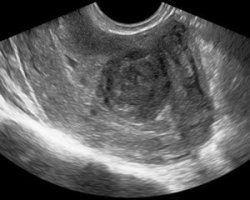

А также может быть проведено трансвагинальное ультразвуковое исследование. Такие методы диагностики при лечении миомы дают возможность определить количество миоматических узлов, их точные размеры, локализацию и плотность. К способам инструментальной диагностики, которая также позволяет уточнить сведения о возникшей доброкачественной опухоли в матке - это гистероскопия - процедура, в ходе которой производится осмотр стенок матки.